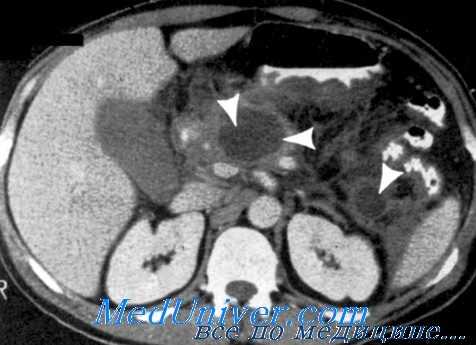

При КТ с контрастным усилением у всех больных АП было обнаружено фокальное или диффузное увеличение поджелудочной железы (ПЖ), нечеткость ее контуров, чуть реже - очаги задержки жидкости в железе (83 %), инфильтрация парапанкреатической клетчатки (70 %), очаги задержки жидкости вне ПЖ плотностью 5-15 ед. и размерами 2-3 см: единичные (18 %), два и более (30 %). В 31,0 % случаев АП изменения, обнаруженные при КТ, соответствовали стадии C по шкале Balthazar-Ranson, в 50,0 % - D, в 19,0 % - E.

При ИП стадию С по шкале Balthazar-Ranson диагностировали в 14,3 %, D - в 18,4 %, E - в 40,8 %. У всех выявлено фокальное или диффузное увеличение ПЖ, нечеткость ее контуров, инфильтрация парапанкреатической клетчатки с наличием секвестров (84,6 %), очаги задержки жидкости в ПЖ - (66,6 %). Очаги скопления жидкости вне ПЖ плотностью 15-20 ед., размерами 5 см и более встречались чаще: единичные в 22,7 %, два и более - 29,5 %.

Компьютерная томография с контрастированием дает косвенные признаки для дифференциальной диагностики асептического и инфицированного панкреонекроза - обширные скопления жидкости вне поджелудочной железы плотностью 15-20 ед. Инфицирование при панкреонекрозе, несмотря на интенсивное консервативное лечение, произошло у трети пациентов. Летальность после оперативного лечения, выполненного в ранние сроки с момента заболевания, была значимо выше, чем после хирургических вмешательств, выполненных в более поздние сроки. Исходом панкреонекроза в 25,3 % было формирование постнекротических (17,6 %) кист и панкреатических свищей (7,7 %).